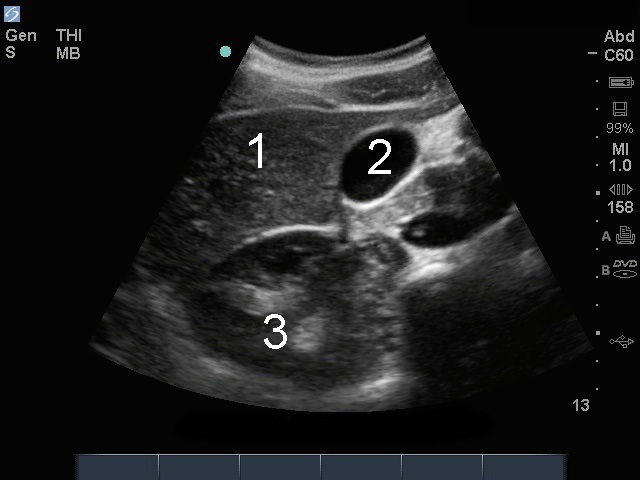

胆嚢横断面画像

肝臓

胆嚢 (GB)

右腎